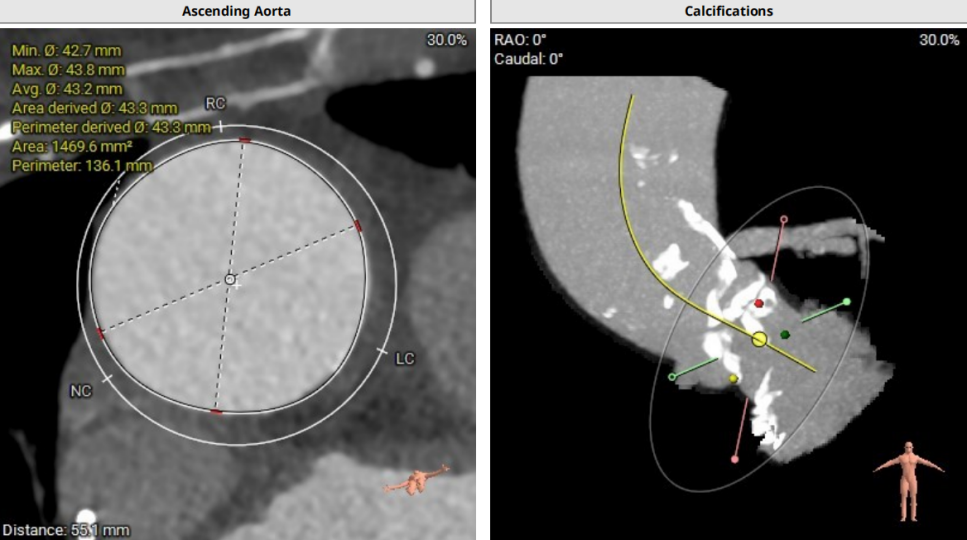

术前CT评估示

瓣环面积:336.2mm²,周长评估直径:20.9mm,面积评估直径:20.7mm。

左室流出道面积:337.4mm²,周长评估直径:21.1mm,面积评估直径:20.7mm。

SOV 直径LC:26.8 mm,RC:27.3mm,NC: 27.1mm,STJ直径26.5mm。

升主动脉平均直径43.3mm,瓣上瓣下均有钙化。

瓣环夹角66°,横位心。